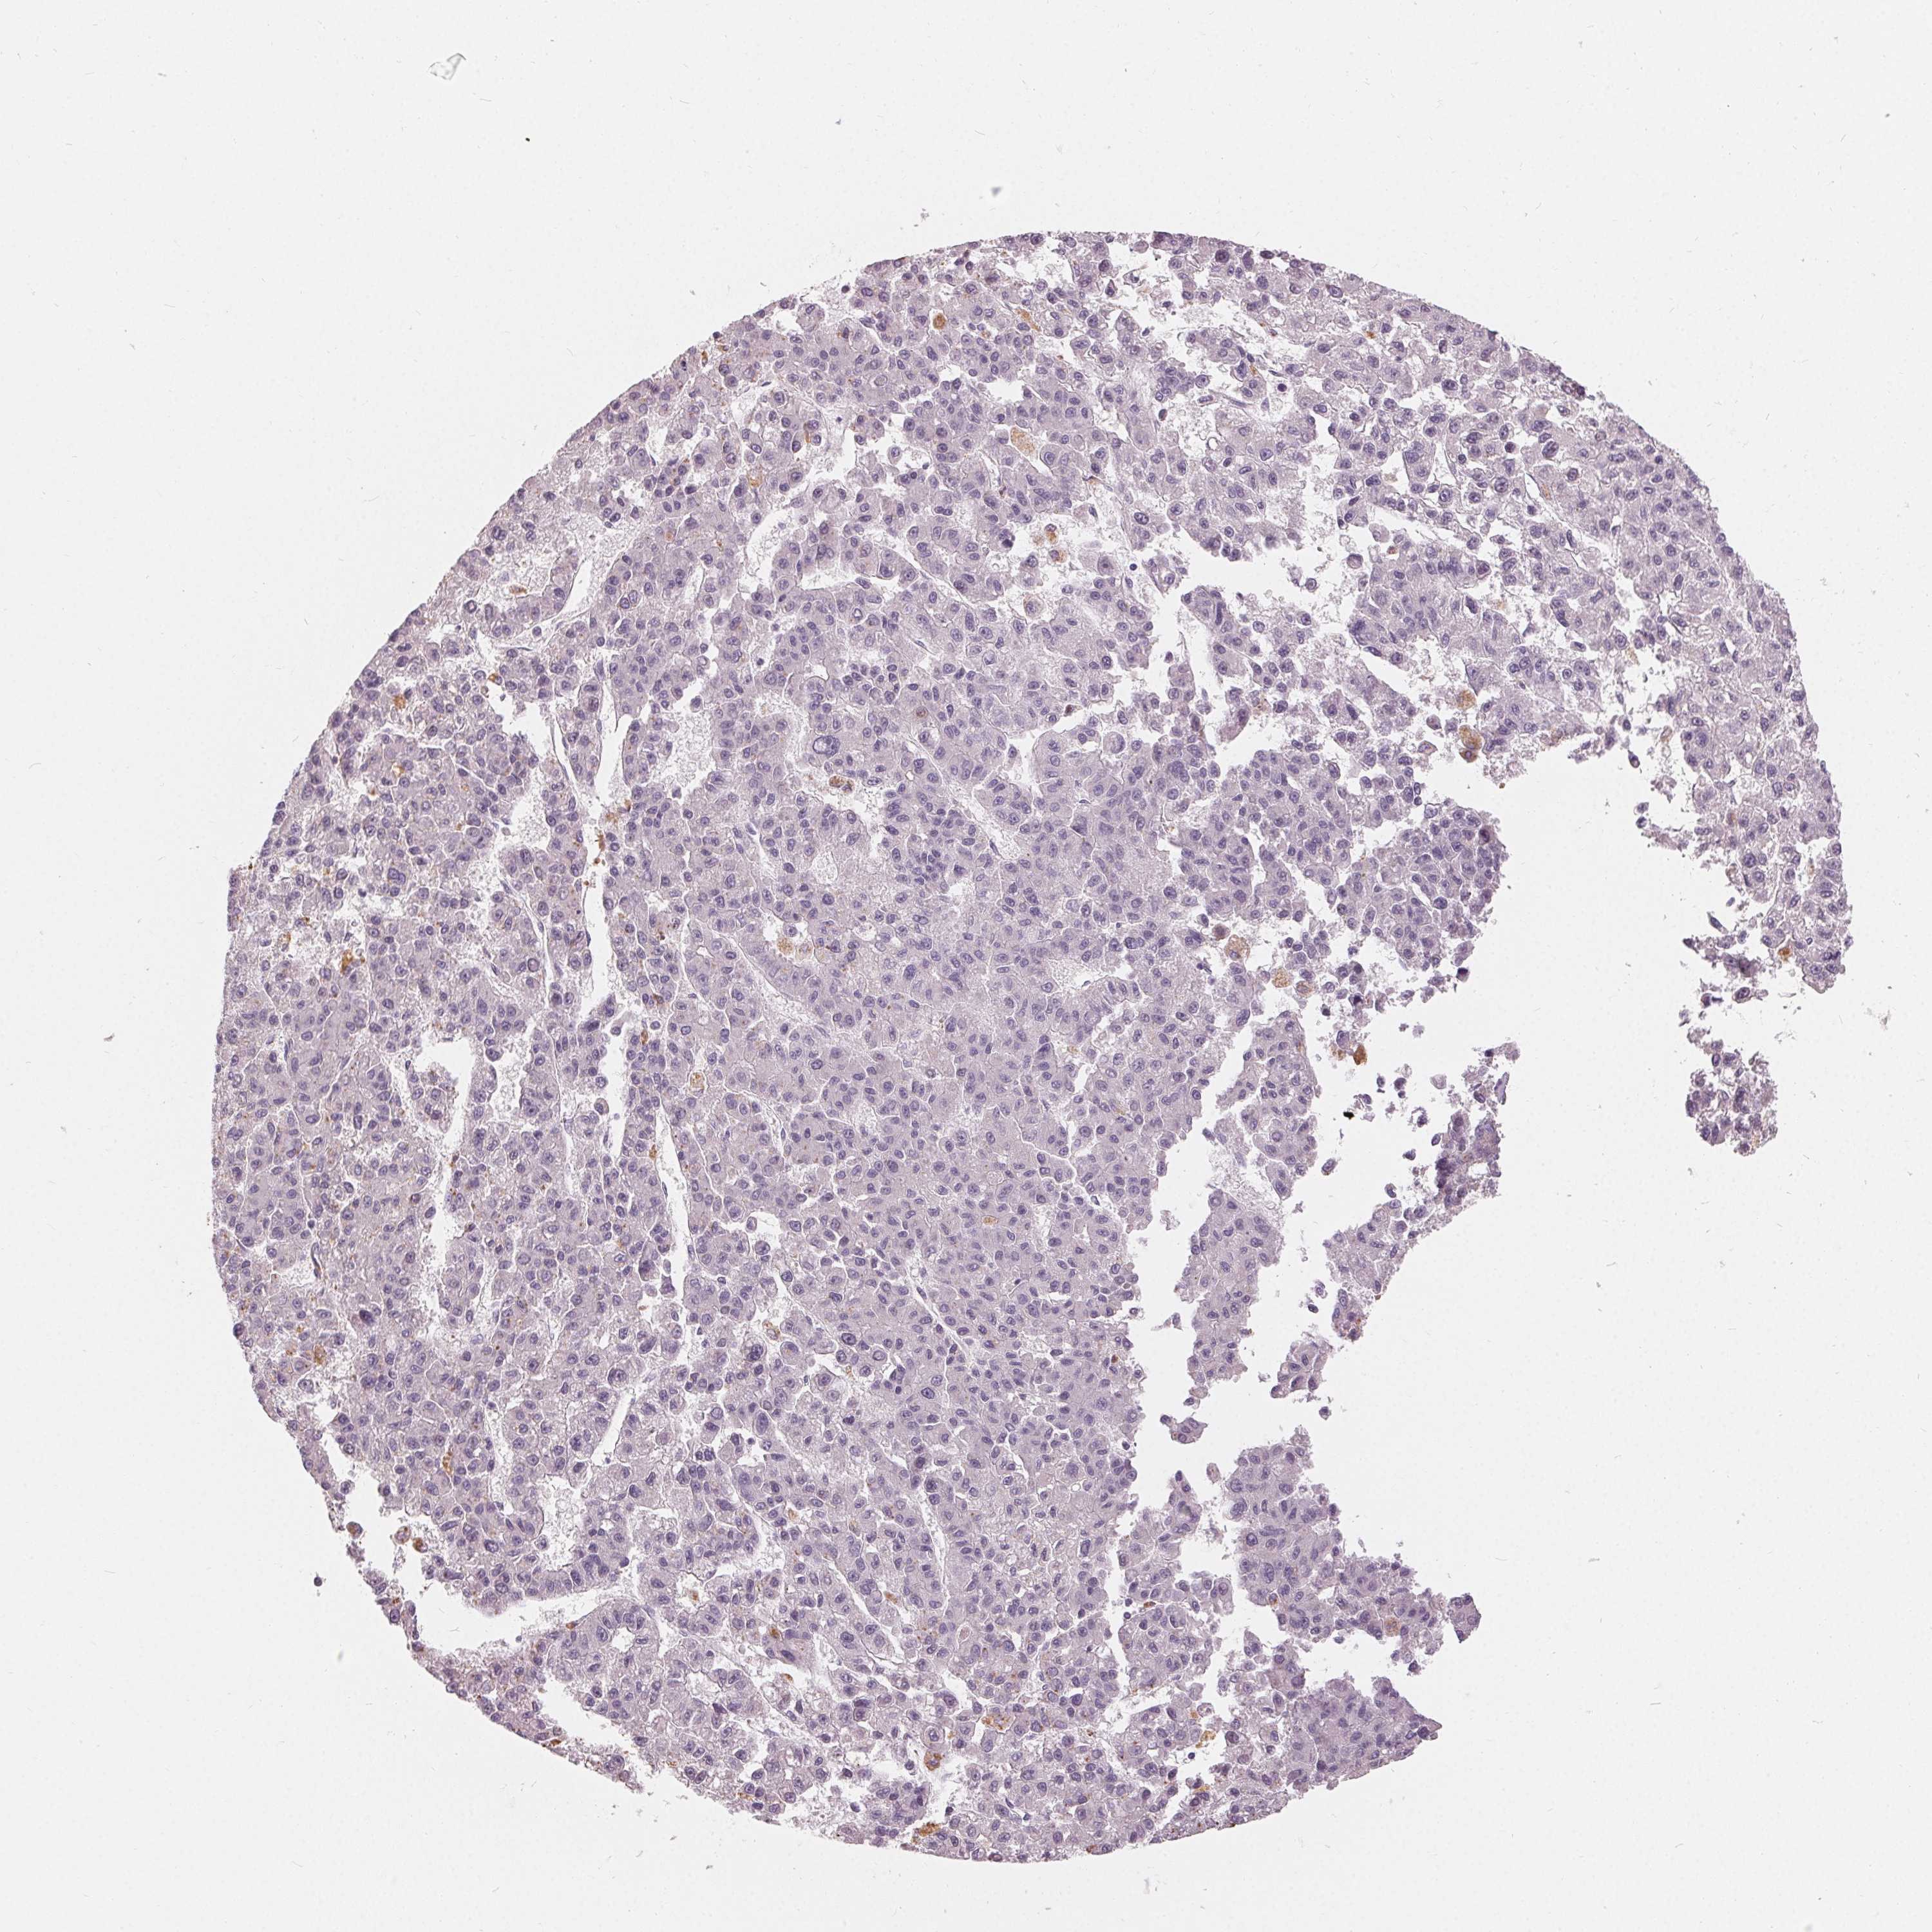

LIVER CANCER - Protein expressioni

A mouse-over function shows sample information and annotation data. Click on an image to view it in a full screen mode. Samples can be filtered based on level of antibody staining by selecting one or several of the following categories: high, medium, low and not detected. The assay and annotation is described here.

Antibody stainingi

Antibody staining in the annotated cell types in the current human tissue is reported as not detected, low, medium, or high, based on conventional immunohistochemistry profiling in selected tissues. This score is based on the combination of the staining intensity and fraction of stained cells.

Each image is clickable and will lead to virtual microscopy that enables deeper exploration of all samples and also displays staining intensity scores, fraction scores and subcellular localization as well as patient and tissue information for each sample.

Antibody HPA030180

Antibody CAB018632

Staining

High

Medium

Low

Not detected

Intensity

Strong

Moderate

Weak

Negative

Quantity

>75%

75%-25%

<25%

None

Location

Nuclear

Cytoplasmic/membranous

Cytoplasmic/membranous,nuclear

Carcinoma, Hepatocellular, NOS

Cholangiocarcinoma